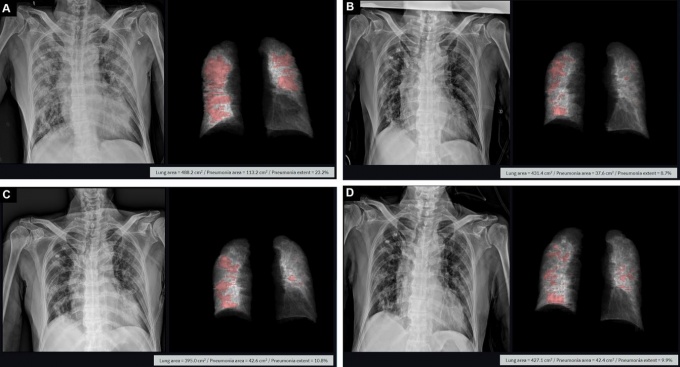

PLOS ONE¿¡ °ÔÀçµÈ Äڷγª19 È®ÁøÀÚ X-ray ¹× Ƽ¼Á Ȱ¿ë Æó·Å ºÐ¼® È­¸é/»çÁøÁ¦°ø=¸ÞµðÄþÆÀÌÇÇ

[µ¥Àϸ®¸Þµð ±¸±³À± ±âÀÚ] ¸ÞµðÄþÆÀÌÇÇ(´ëÇ¥ ¹Ú»óÁØ)°¡ ÀÚ»ç ¼Ö·ç¼Ç 'Ƽ¼Á'À» Ȱ¿ëÇØ ¿¢½º·¹ÀÌ ¿µ»ó¿¡¼­ ½ÅÁ¾ Äڷγª¹ÙÀÌ·¯½º °¨¿°Áõ(Äڷγª19) Æó·ÅÀ» Á¤·®È­ÇÑ ¿¬±¸ ³í¹®À» ÀÇÇÐ ±¹Á¦ÇмúÁö ‘PLOS ONE’¿¡ °ÔÀçÇß´Ù°í 27ÀÏ ¹àÇû´Ù.

¸ÞµðÄþÆÀÌÇÇ´Â °ü°èÀÚ´Â "Ƽ¼ÁÀ» Ȱ¿ëÇØ Äڷγª19 ÈäºÎ ¿¢½º·¹ÀÌ »çÁø¿¡¼­ Æó ¼Õ»ó Á¤µµ¸¦ ¼öÄ¡·Î ºÐ¼®ÇÏ°í º´Áõ ÃßÀ̸¦ °èÃþÈ­ÇØ »ç¸Á À§Çèµµ¸¦ ¿¹ÃøÇÒ ¼ö ÀÖ´Ù´Â °¡´É¼ºÀ» È®ÀÎÇß´Ù"°í ¸»Çß´Ù.

Ƽ¼ÁÀº Äڷγª19 Æó·Å º´º¯ÀÌ Â÷ÁöÇÏ´Â ºñÀ²À» 3Â÷¿ø Á¤º¸·Î Á¤·ÉÈ­ÇÏ´Â ¼Ö·ç¼ÇÀÌ´Ù. º´º¯À» ÀÚµ¿À¸·Î ºÐÇÒÇÏ°í ¼öÄ¡È­ÇØ °´°üÀûÀÎ Áúº´ Á¤º¸¸¦ ¾òÀ» ¼ö ÀÖÀ¸¸ç À̸¦ ±â¹ÝÀ¸·Î Àå±âÀûÀ¸·Î Ä¡·á °æ°ú¸¦ È®ÀÎÇÒ ¼ö ÀÖ´Ù.

ƯÈ÷ Äڷγª19 »Ó¸¸ ¾Æ´Ï¶ó Æó°áÇÙ(TB) µî °¢Á¾ Æó ÁúȯÀ» ½Å¼ÓÇÏ°Ô ÆÇµ¶, Á¤·®È­Çϰí Ä¡·á È¿°ú¸¦ °üÂûÇÒ ¼ö ÀÖ´Ù´Â °Ô °ü°èÀÚ ¼³¸íÀÌ´Ù.

¿¬±¸¸¦ ÁÖµµÇÑ À±¼øÈ£ ¼­¿ï´ëÇб³º´¿ø ¿µ»óÀÇÇаú ±³¼ö´Â “Äڷγª19 Æó·Å Áõ¼¼ ±ËÀûÀ» ºÐ¼®ÇÏ°í °üÂûÇØ °íÀ§Çè ȯÀÚ¸¦ ½Å¼ÓÇÏ°Ô Á¶Ä¡ÇÒ ¼ö ÀÖÀ» °Í"À̶ó°í ¸»Çß´Ù.

¹Ú»óÁØ ´ëÇ¥´Â “¼¼°èº¸°Ç±â±¸¿¡¼­µµ Äڷγª19 ÁßÁõ ȯÀÚ Áø´Ü¿¡ ÈäºÎ ¿¢½º·¹ÀÌ È°¿ëÀ» ±Ç°íÇϰí ÀÖ´Ù"¸ç "¾ÕÀ¸·Î »ç¸ÁÀ§Ç豺À» °èÃþÈ­ÇØ ¼±º°ÀûÀ¸·Î °ü¸®ÇÏ´Â Çõ½Å±â¼ú·Î ÀÚ¸®ÀâÀ» °Í"À̶ó°í ÀüÇß´Ù.